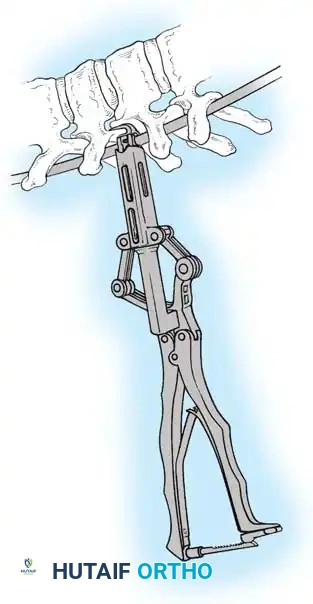

Fig. 38-26: The Moe technique of thoracic facet fusion, demonstrating the creation of hinged bone flaps.

- Expose the spine fully to the tips of the transverse processes.

- Using a sharp osteotome or Cobb gouge, begin a cut over the cephalad articular process at the base of the lamina.

- Carry this cut along the transverse process almost to its tip. Bend this cortical fragment laterally so it lies between the transverse processes, ideally leaving it hinged on its lateral periosteal attachment to preserve local vascularity.

- Thoroughly denude all articular cartilage from the superior articular process using a sharp curet.

- Make a secondary cut in the superior articular facet, working medially to laterally, producing another hinged fragment.

- Pack the resulting intra-articular defect tightly with cancellous bone graft.